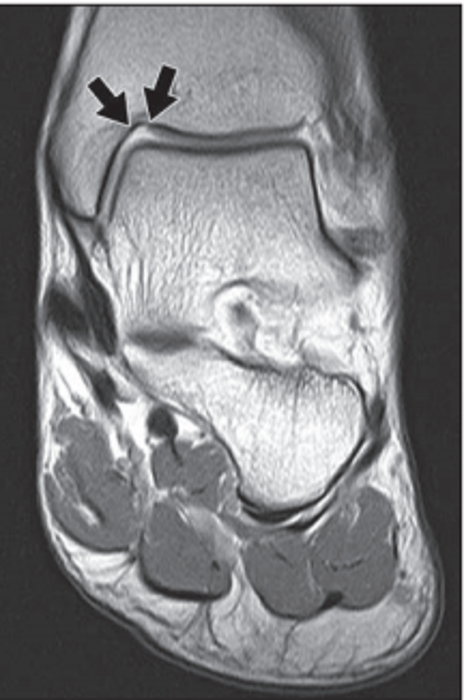

periosteal desmoid

Periosteal desmoid aka cortical desmoid aka distal femoral metaphyseal irregularity (many different names-yay). This is basically an avulsion injury 2/2 repeated microtrauma. Classic location is an eccentric cortical lucency in the medial femoral metaphysis. Usually young males, and commonly bilateral.